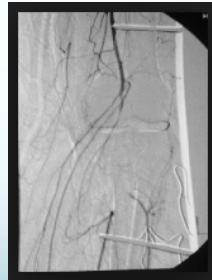

Vascular Assessment:

- Even if pulses are intact, perform angiography if there’s suspicion

- Angiography if distal pulses not felt